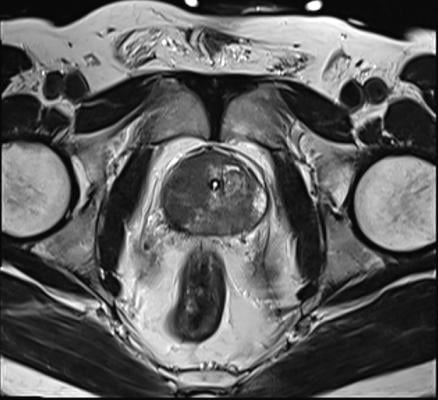

April 10, 2024 — Blue Earth Therapeutics, a Bracco company and emerging leader in the development of innovative next generation therapeutic radiopharmaceuticals, today announced results from a series of preclinical analyses designed to identify synergistic combinations of known anticancer drugs with 177Lu-rhPSMA-10.1 radioligand therapy, and from a preclinical efficacy analysis of the lead novel drug combination for the treatment of prostate cancer. Results from a systematic in vitro screen identified MEK inhibitor cobimetinib as a lead candidate with potential for synergistic combination with 177Lu-rhPSMA-10.1, and the preclinical efficacy analysis showed enhanced therapeutic effect of this drug combination when compared to the untreated control and to the single agents alone. The data were presented in a poster presentation at the American Association for Cancer Research (AACR) Annual Meeting 2024 in San Diego, Calif. 177Lu-rhPSMA-10.1, an investigational radiohybrid (rh) Prostate-Specific Membrane Antigen-targeted therapeutic radiopharmaceutical, is the lead candidate in Blue Earth Therapeutics’ oncology development program of next generation therapeutic radiopharmaceuticals.

More than 150 FDA-approved anticancer drugs were screened in a clonogenic survival assay of 22Rv1 cells using the test drug alone, at a range of concentrations <20 µM to determine the IC50. The results were then compared to incubations of the drug plus 15 MBq/mL 177Lu-rhPSMA-10.1 (2-hour incubation) after 10 days. Five lead candidates were then selected for a focused screen where the impact of 177Lu-rhPSMA-10.1 (0–25 MBq/mL) on the drug IC50 was determined. A synergy score was determined using the zero interaction potency (ZIP) reference model and the multi-dimensional synergy of combinations (MuSyc) platform. Therapeutic efficacy of the lead combination, 177Lu-rhPSMA-10.1 (single 30 MBq iv dose) plus cobimetinib (0.25 mg orally per day for 21 days), was then evaluated in 22Rv1 prostate tumor xenograft models and compared to the single agents alone (n = 8 per group, plus untreated controls). Tumor volume was measured 2 times per week for 69 days. Two-way ANOVA and Tukey’s multiple comparisons test (data analyzed until n = 3 remained per group) and Kaplan-Meier Log-rank survival analyses were performed.

The in vitro screen identified the MEK inhibitor cobimetinib as a lead candidate for synergistic combination with 177Lu-rhPSMA-10.1 across a wide concentration range, with a ZIP synergy score of 13.25% (95% CI ± 2.17) and promising results on MuSyc analysis. The 177Lu-rhPSMA-10.1 plus cobimetinib MEK inhibitor combination significantly suppressed tumor growth in vivo versus untreated controls (from day 13–30; p<0.01) and 177Lu-rhPSMA-10.1 alone (from day 17–30; p<0.001). The median survival in the combination group (49 days) was significantly longer versus the untreated group (23 days; p=0.001) and the group treated with 177Lu-rhPSMA-10.1 alone (36 days; p=0.002).